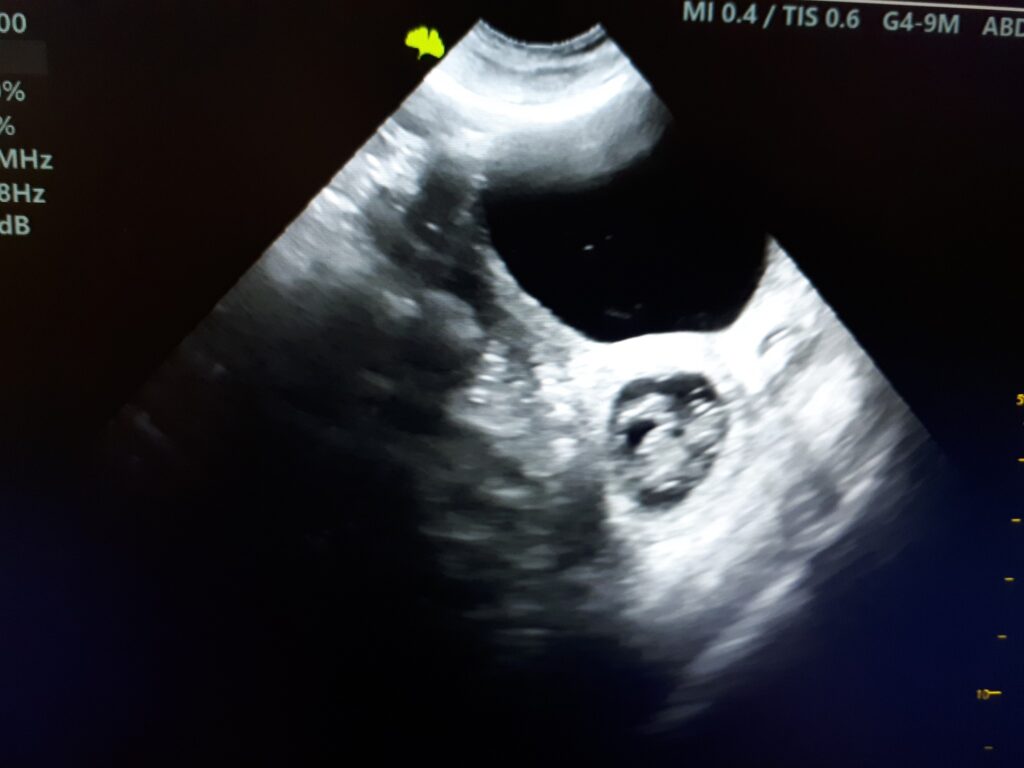

Hurra, ciąża potwierdzona !!!

Kolejna ciąża potwierdzona. Trzymamy kciuki! Dodaj tu swój tekst nagłówka